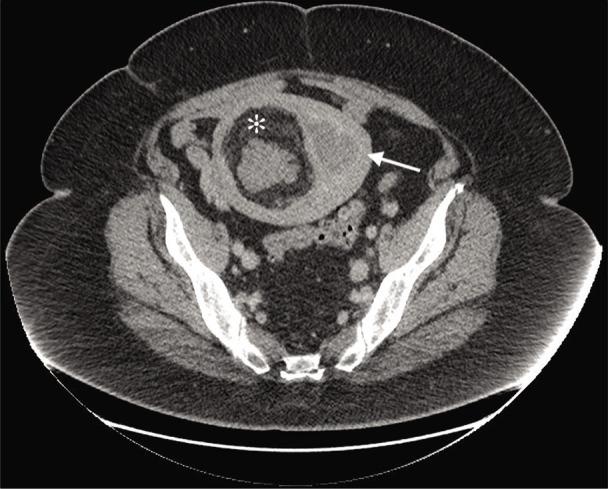

We describe a case of a 63-year-old woman referred to an oncologist for treatment of endometrial adenocarcinoma. A computed tomography scan revealed the incidental finding of a 11.5 × 10.5 × 9.0 cm myomatous mass in the uterine corpus adjacent to, yet uninvolved with, the adenocarcinoma. Histopathological analysis confirmed the mass to be a lipoleiomyoma, a rare single variant of lipoma. These fatty tumors present similar to leiomyomas and as such are generally not harmful; however, the potential exists for diagnostic confusion with other uterine tumors. This case serves to further illuminate the findings associated with these rare tumors.

我们描述了一例63岁女性因子宫内膜腺癌转诊至肿瘤学家处接受治疗的病例。计算机断层扫描偶然发现子宫体有一个11.5×10.5×9.0厘米的肌瘤样肿块,与腺癌相邻但未受其影响。组织病理学分析证实该肿块为脂肪平滑肌瘤,这是一种罕见的脂肪瘤单一变体。这些脂肪性肿瘤的表现与平滑肌瘤相似,因此通常无害;然而,与其他子宫肿瘤存在诊断混淆的可能性。本病例有助于进一步阐明与这些罕见肿瘤相关的发现。